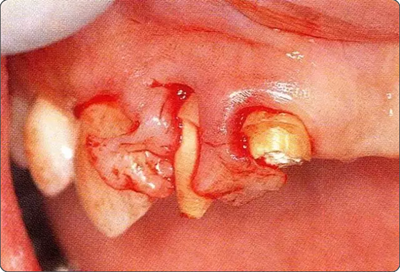

圖10-3  考慮到審美性,應(yīng)用牙齦乳頭保存術(shù)(Papilla preservation technique),進(jìn)行了自體骨移植。